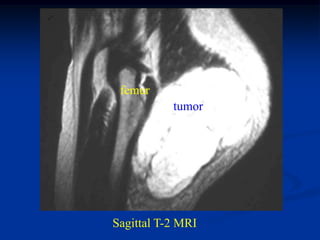

femur

tumor

Sagittal T-2 MRI